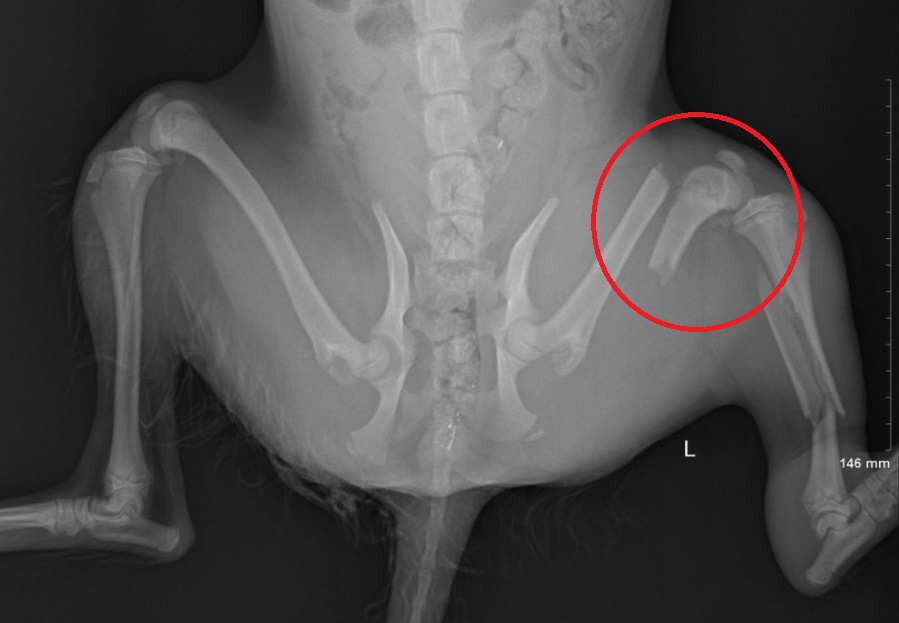

新北動保處指出,動保員將受傷的狗狗帶回「毛寶貝醫療中心」後,就立刻展開一連串的醫療流程,並由動保處殷書韻獸醫師診斷後發現狗狗傷勢嚴重,左後肢股骨骨折以及脛骨粉碎性骨折,必須立即安排手術,將兩處骨折接回原處,術後經過獸醫師親自每日投藥加上復健,狗狗復原速度相當快,過了5天就可以順利走動,負責救援的張姓動保員也開心的每天都帶牠外出散步,並將牠取名為「安妮」。

殷書韻醫師表示,狗狗發生車禍骨折是很常見的事,但快速的康復主要是因為動保處在第一時間前去救援,才能夠在最短的時間內將粉碎的骨頭接回,再加上「安妮」年紀很小,本身就有很好的復原能力。殷書韻也強調,只要是救援進來動物醫療中心的動物,醫療團隊都一定會竭盡所能的醫治,但務必要把握黃金救援時刻,才可以提升救援成功機率。